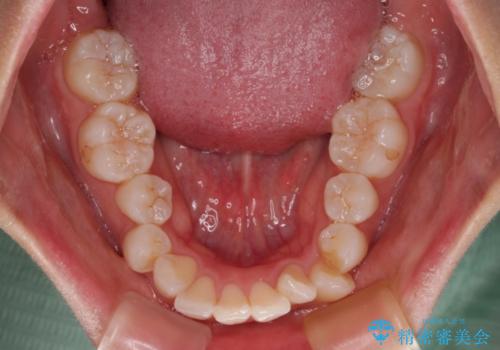

- 口を閉じたときに飛び出してしまう上顎前歯を気にして来院された患者様です。

下顎はデコボコが気になっていたため、上下左右第一小臼歯4本を抜去して、ワイヤー装置にて口元の突出感を改善するよう矯正治療を行うこととしました。

下唇に前歯が当たって跡が残ってしまう状態でしたが、スッキリとした口元に仕上げることができました。